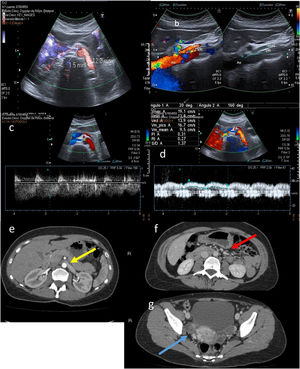

The most significant Doppler findings are duplication of PSV compared to its value at rest in the subclavian artery and loss of respiratory dynamics in the subclavian vein in 90-degree abduction. Complete cessation of arterial and/or venous blood flow in hyperabduction indicates complete occlusion.2,3 Another finding is attenuation of radial flow with Allen's and Adson's manoeuvres (Fig. 4).

A) Normal arterial blood flow in a neutral position of the subclavian artery. B) Duplication of PSV in the subclavian artery in 90-degree abduction in thoracic outlet syndrome (TOS). C) Normal venous blood flow in a neutral position of the subclavian vein. D) Loss of respiratory dynamics in the subclavian vein with abduction manoeuvres in TOS. E) Normal radial artery wave in a neutral position and attenuated with Adson's manoeuvre in TOS. F) Contrast-enhanced computed tomography, in a coronal projection, showing left subclavian artery compression in the costoclavicular region.